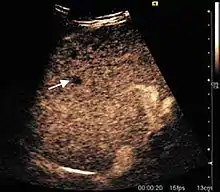

It is the most common liver tumor with a prevalence of 0.4 – 7.4%. It is generally asymptomatic but also can be associated with pain complaints or cytopenia and/or anemia when it is very bulky. It is unique or paucilocular. It can be associated with other types of benign liver tumors. Characteristic 2D ultrasound appearance is that of a very well defined lesion, with sizes of 2–3 cm or less, showing increased echogenity and, when located in contact with the diaphragm, a "mirror image" phenomenon can be seen. When palpating the liver with the transducer the hemangioma is compressible sending reverberations backwards. Doppler exploration reveals no circulatory signal due to very slow flow speed. CEUS investigation has real diagnosis value due to the typical behavior of progressive CA enhancement of the tumor from the periphery towards the center. The enhancement is slow, during several minutes, depending on the size of hemangioma and on the presence (or absence) of internal thrombosis. During late (sinusoidal) phase, if totally "filled" with CA, hemangioma appears isoechoic to the liver. Deviations from the above described behavior can occur in arterialized hemangiomas or those containing arterio-venous shunts. In these cases, differentiation from a malignant tumor is difficult and requires other imaging procedures, follow up and measurements of the tumor at short time intervals.[1]